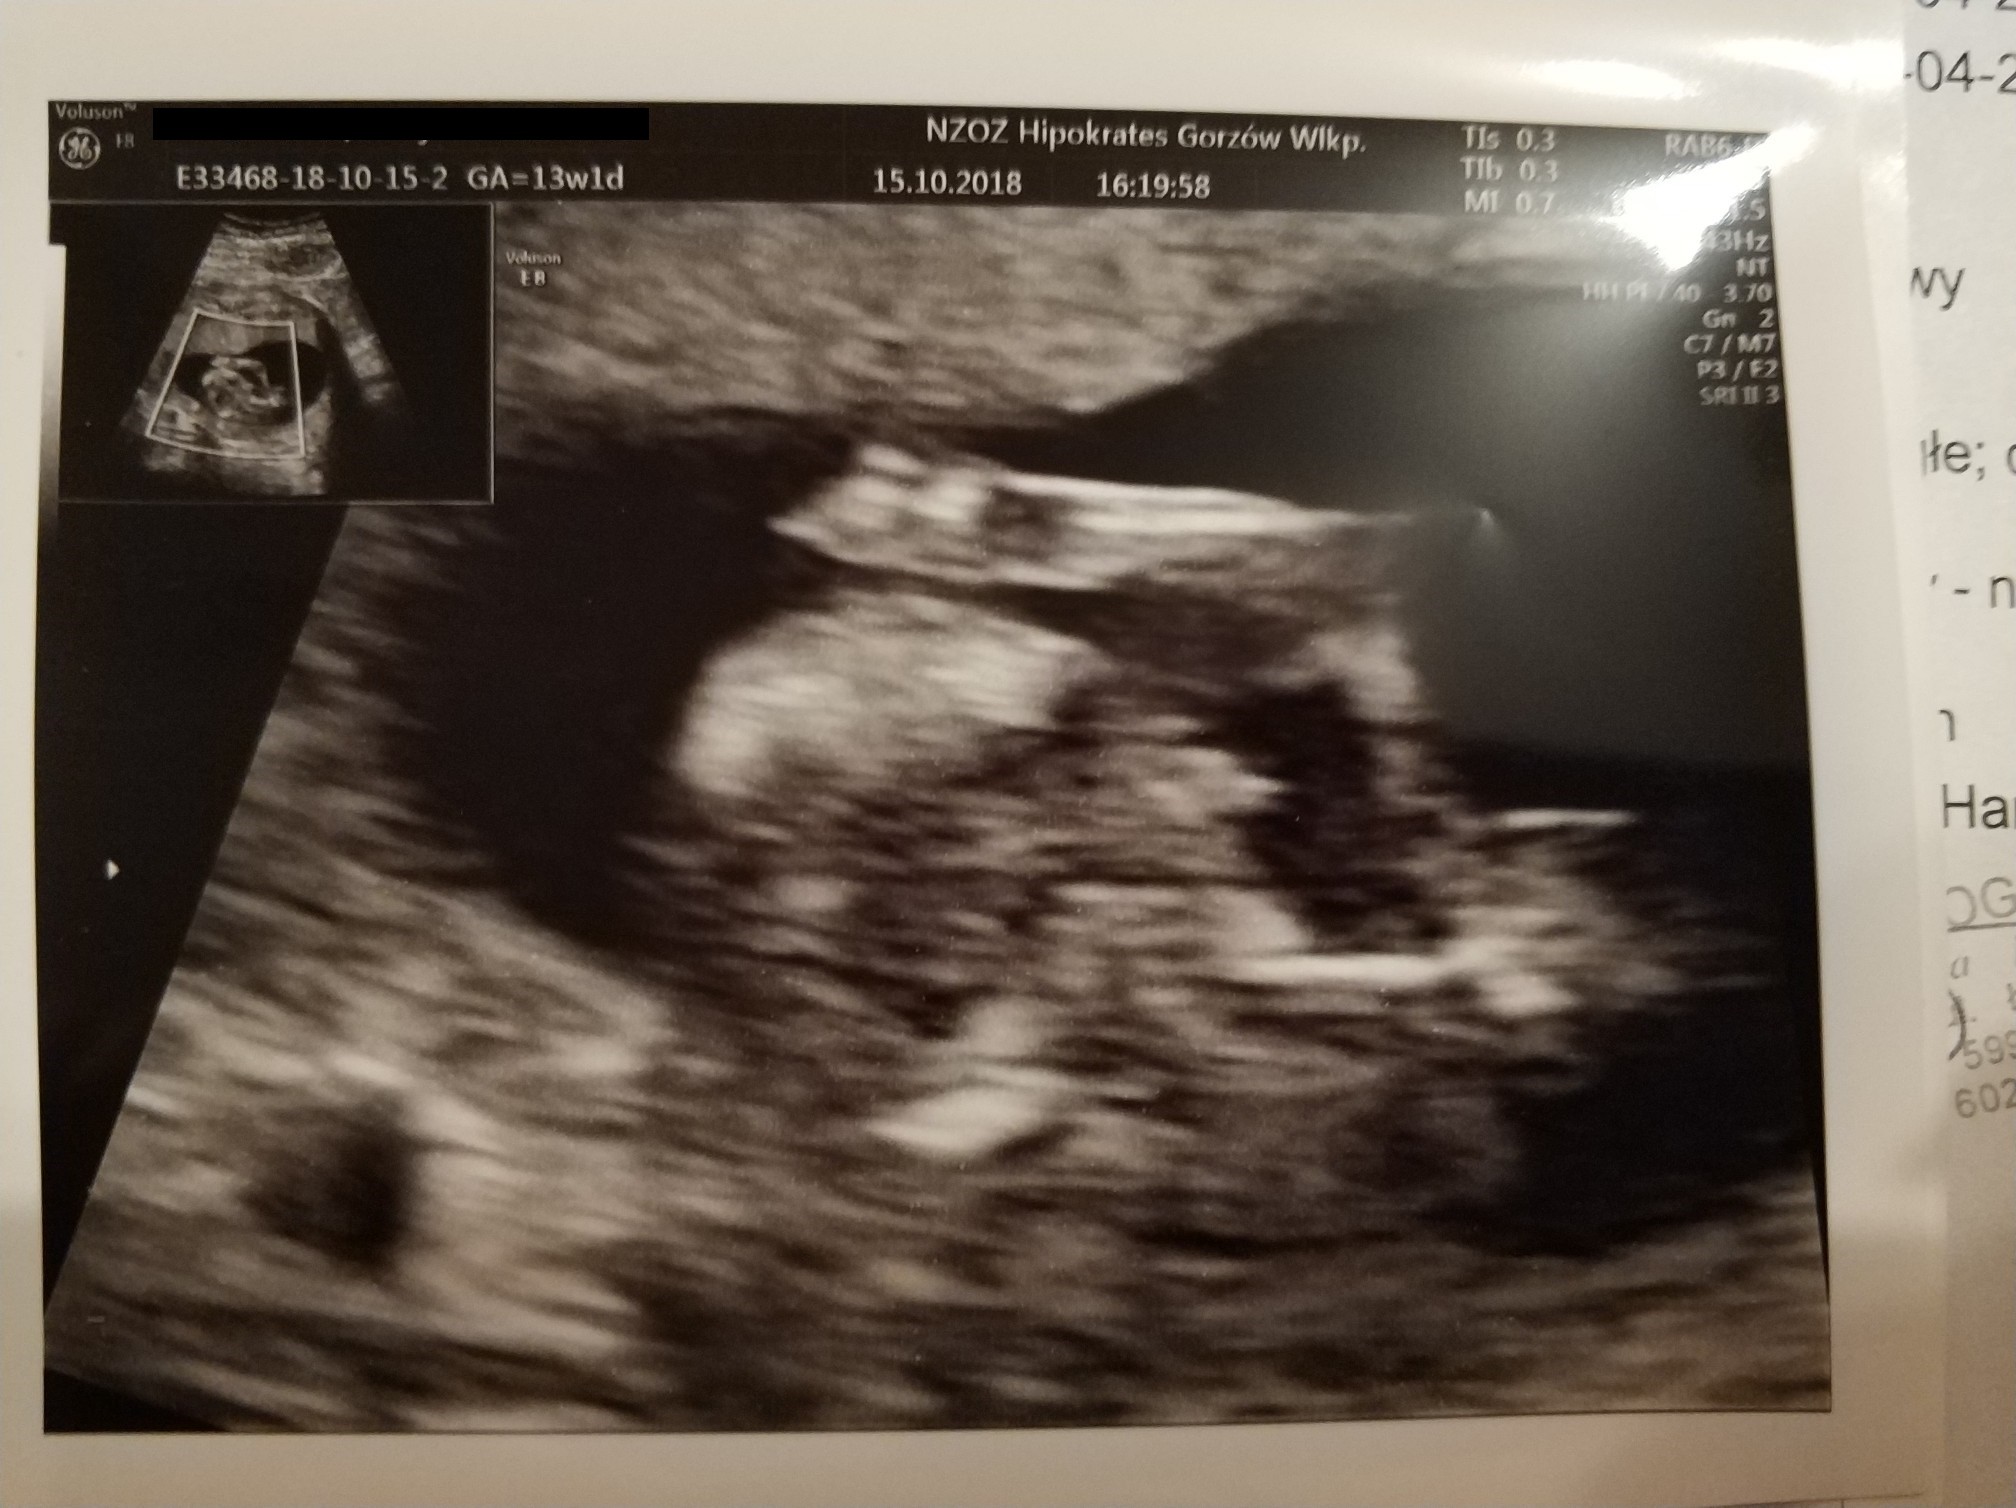

Moje prenatalne wwyszly prawidlowo. dzidzia ma 63mm, odpowiada 12+5, glowka w normie wielkoscia jak z OM 13+1.

serduszko 160u/min w koncu moglam uslyszec!! :)

pecherzyk ciazowy: owalny , NT: 2,2

zarys tułowia: prawidlowy, kosc nosowa: widoczna. Termin porodu 21 kwietnia.

obraz "motyla" mózgu prawidlowy, powloki jamy brzusznej ciagle, cewa nerwowa szczelna, spektrum przeplywu przez zastawkę trojdzielna i przewod zylny - nie do oceny. no i tutaj musze wam powiedziec masa wzruszen byla. dzidzioł tak fikal krecil sie i skakal ze nie szlo go badac. musialam sie obkrecac, kaszlec prowokowac czorta malego.. Pani dr stwierdzila ze niezly skoczek zamieszkuje.

No i prawdopodobnie synek ale mowila zeby jeszcze spokojnie podchodzic do tego.

jestem zadowolona z badania Pani ladnie tlumaczyla, monitor swoj mialam nad glową i wszystko moglam sledzic.

zalaczam kilka fotek :)